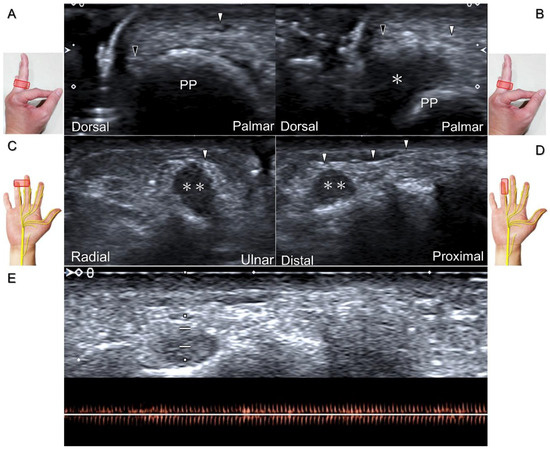

Clinical Implication

Injuries to the dorsal common digital nerve typically occur in the workplace as a result of cutting or crushing. However, the nerve can also sustain damage due to various other factors such as fracture, ganglia, tenosynovitis, tumor (Figure 34), foreign objects, or boxing, which may cause contusion over the first knuckles (Figure 35).

US imaging may reveal a neuroma in cases where patients report chronic allodynia and/or tingling sensation in the affected digit (Figure 36). To perform hydrodissection, the in-plane approach can be utilized in the nerve’s short axis after identifying the extensor digitorum tendons and the dorsal metacarpal arteries (Figure 37).

Figure 34. In the short-axis view, the proper digital nerve is seen as irritated by a giant cell tumor (A) with increased vascular signals (B). The association between the proper digital nerve and the tumor is delineated in the long-axis view (C). Black arrowheads: proper digital nerve; PP: proximal phalanx; *: giant cell tumor.